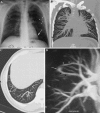

This pictorial review is based on our experience of the follow-up of 120 patients at our multidisciplinary center for hereditary hemorrhagic telangiectasia (HHT). Rendu-Osler-Weber disease or HHT is a multiorgan autosomal dominant disorder with high penetrance, characterized by epistaxis, mucocutaneous telangiectasis, and visceral arteriovenous malformations (AVMs). The research on gene mutations is fundamental and family screening by clinical examination, chest X-ray, research of pulmonary shunting, and abdominal color Doppler sonography is absolutely necessary. The angioarchitecture of pulmonary AVMs can be studied by unenhanced multidetector computed tomography; however, all other explorations of liver, digestive bowels, or brain require administration of contrast media. Magnetic resonance angiography is helpful for central nervous system screening, in particular for the spinal cord, but also for pulmonary, hepatic, and pelvic AVMs. Knowledge of the multiorgan involvement of HHT, mechanism of complications, and radiologic findings is fundamental for the correct management of these patients.